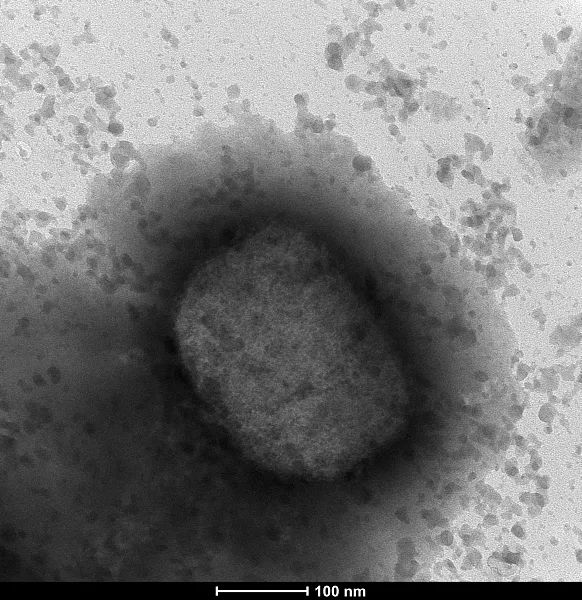

6、世卫组织举行紧急会议“在英国西班牙和葡萄牙有多例确诊病例,这是欧洲有史以来规模最大范围最广的猴痘爆发”德国武装部队的医疗服务部门周五表示,该部门发现了德国的首例病例来自罗伯特#8231科赫研究所的法比安#。

7、与此同时,世界卫生组织WHO周五20日召开了紧急会议,讨论这场最近“前所未有”的疫情世卫组织表示,情况正在发生变化,世卫组织预计随着监测在非流行国家的扩大,将会发现更多的猴痘病例据外媒21日报道,WHO驻欧洲。

13、目前已有48个国家和5个世卫组织地区发现了这种病毒,病例人数可达3200多例,多个国家已经向世界卫生组织表示猴痘这种病毒已经出现了在社区传播的现象,这就很有可能会造成猴痘病毒的聚集性传播,传播面积的增大,也是从侧面反映出。

14、近日在非洲多个国家发现的新型变异新冠病毒引起各国高度警惕,世界卫生组织11月26日举行紧急会议后发布声明,将这种新型新冠病毒变异株列为“需要关注的变异株”,并命名为奥密克戎Omicron世卫组织在声明中指出。

15、针对世卫组织的言论,引起了人们的广泛关注,大家纷纷担心猴痘病毒会不会成为下一个新冠毕竟这种病毒可以在人之间传播,而且速度非常的快所以人们的担心不无道理,病毒的预防需要重视世卫组织也准备召开第二次紧急会议。